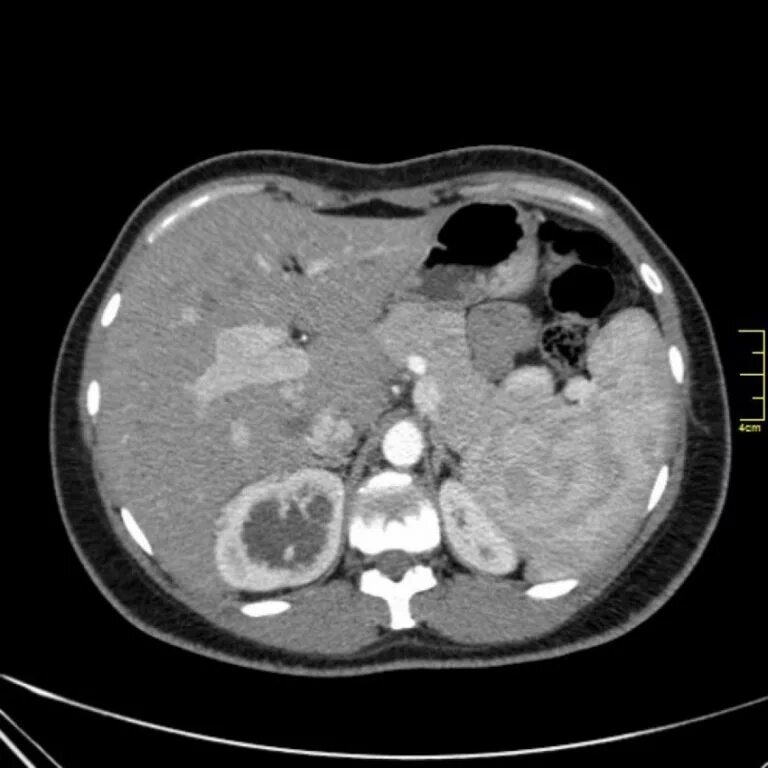

Пиелонефрит кт